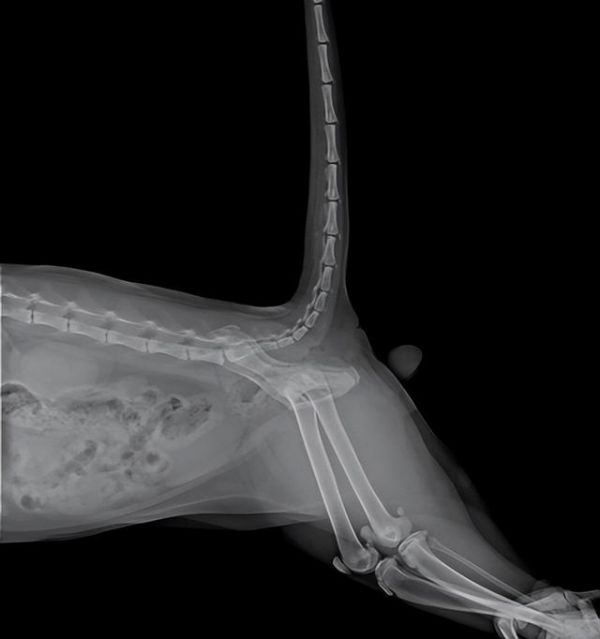

大型犬髋关节发育不良

通常来说我们会区分狗跟猫咪,中大型犬最常见的像是:拉布拉多、金毛、德牧、二哈、阿拉斯加,它们可能从小就会有先天的髋关节发育不良,还有就是老年犬也比较容易会有一些退化性的关节问题。

脊椎问题

像是巴哥或者法斗这类型的犬种,它们一般都会有一些半椎体的问题,而像是柯基、腊肠犬这些它们都会有一些脊椎方面的问题,这些也是会跟椎间盘、关节部分也会有相关的状况,一般表现狗狗不太爱走路有趴窝的情况发生。